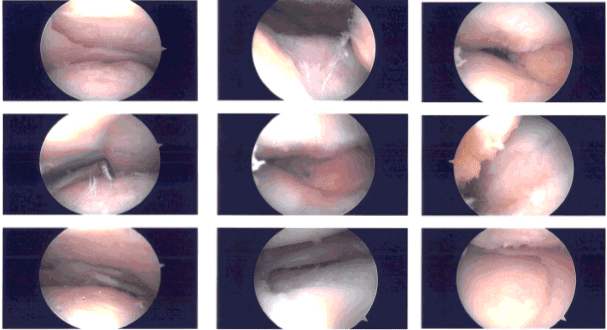

Se realizó un examen de la rodilla, que mostró una ruptura del margen de liberación lateral del menisco medial, así como una ruptura del margen de liberación medial del menisco lateral junto con el menisco lateral discoide. El LCA estaba intacto. La meniscectomía se realizó con el uso de mordedores y afeitadores.

También se confirmó la saucerización del menisco lateral. La raíz, así como la periferia del menisco medial y lateral, permanecieron intactas. El LCA estaba intacto.

El examen de la articulación patelofemoral mostró artritis de grado 1 a grado 2 en la faceta lateral de la rótula, así como artritis de la troclea de grado 3 a grado 4. La condroplastia de rótula y troclea se realizaban con el uso de afeitadora y varita de coblación. Se tomaron y guardaron las fotos finales.

Imágenes intraoperatorias